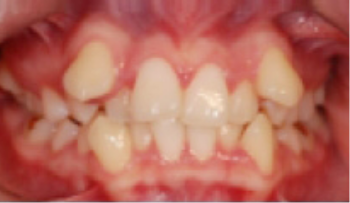

• 총생(Crowding) 치아가 삐뚤게 남.

Before

After